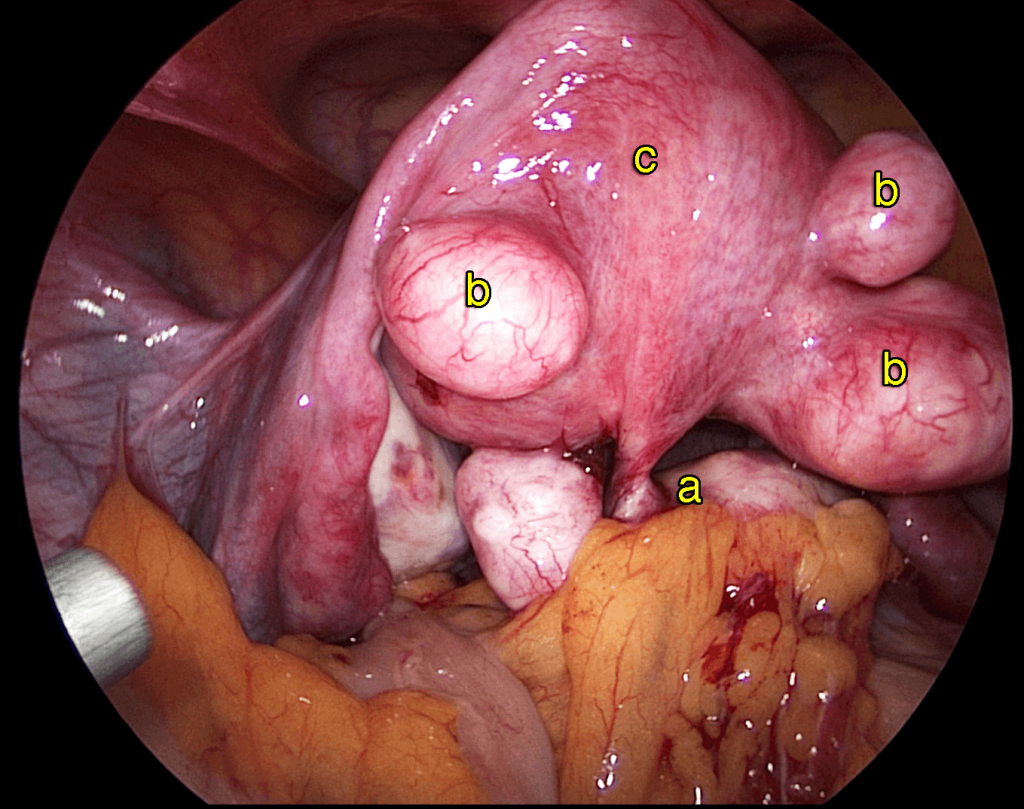

Women’s health requires a thoughtful and personalized approach at every stage of life. Our gynecology services are designed to diagnose, manage, and treat a wide range of gynecological conditions with accuracy, compassion, and advanced medical expertise. We provide comprehensive care for issues such as menstrual irregularities, pelvic pain, hormonal imbalances, reproductive health concerns, infections, fibroids, ovarian cysts, and other common and complex gynecological conditions.